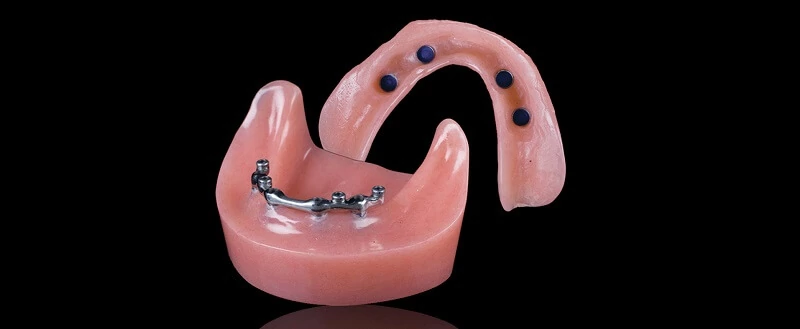

Современные методы протезирования зубов: Рекомендации и советы